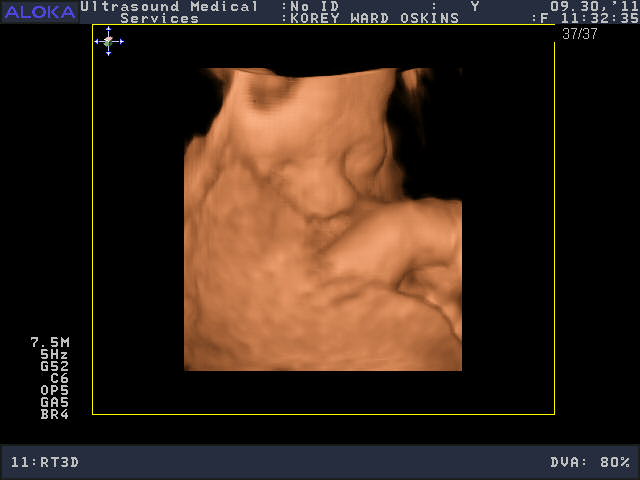

He was a very stubborn baby, so it was really kind of nerve-wracking at first thinking we might not get a single good picture. His face was squished up against the placenta and he wouldn’t budge. You’ll see that in the pictures below; it looks like an enveloping cloud or a scallop shell. Finally he moved a bit and we got some glimpses of his face. We saw him make some facial expressions, wiggle his fingers, and move his mouth around. We were curious to see whose nose he would have, and in some pictures, it looks like he has Josh’s, in others, mine.

So who do you think he looks like?

He is sooooo cute! Personally, I think he looks like ME.